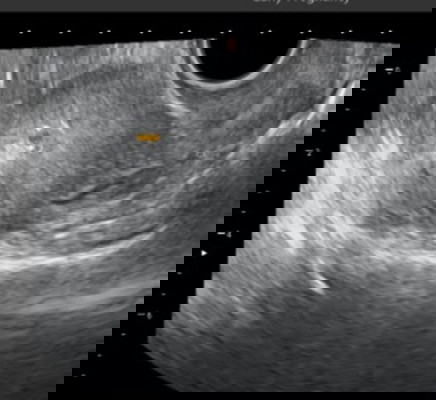

Hamil 5 minggu kantung baru terlihat 0,53 cm apakah normal?

Selamat siang bunda,mau brtnya ni bun siapa tau pengalamanny ada sama sprti saya, saat ini sya sdh telat 2 mnggu, hpht sya tgl 15 sept, sya usg transvaginal prtama stelah tp + tgl 20 okt hasilny trlihat pnebalan dinding rahim dan d ksh obat penguat microgest 200 mg d mnumny 2x sehari,dan vitamin, lalu usg kdua tgl 26 okt dan terlihat kantung ukuranny 0,53 cm via usg transvaginal, harusny saat itu udh usia ny 5 mngguan, tp klo lht dr hasil usg blm smpe 5 mnggu kata dokterny..apa ini termasuk normal y bun ukuranny saat itu hanya 0,53 cm sperti yg trlihat d foto usg ini? Dan apakah bunda ada yg pernah d ksh obt penguat microgest 200 mg d sruh minumny 2 kali sehari pagi sm malem? #bantusharing #sharingpengalaman